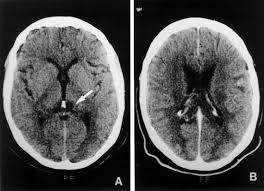

- Tomografia axial computerizada (TAC): permite detectar la localización del tumor, las alteraciones que hayan podido darse. En la realización de esta prueba hace falta la toma de contrastes que favorezcan las estructuras.